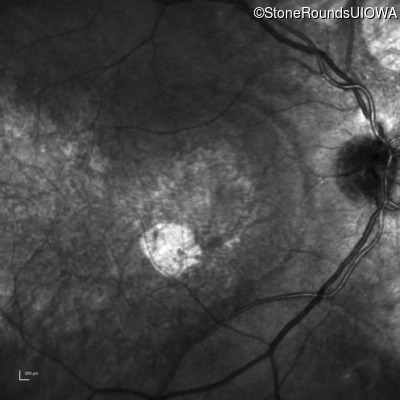

Infrared Fundus Photograph - Right - 20/100

Exemplar